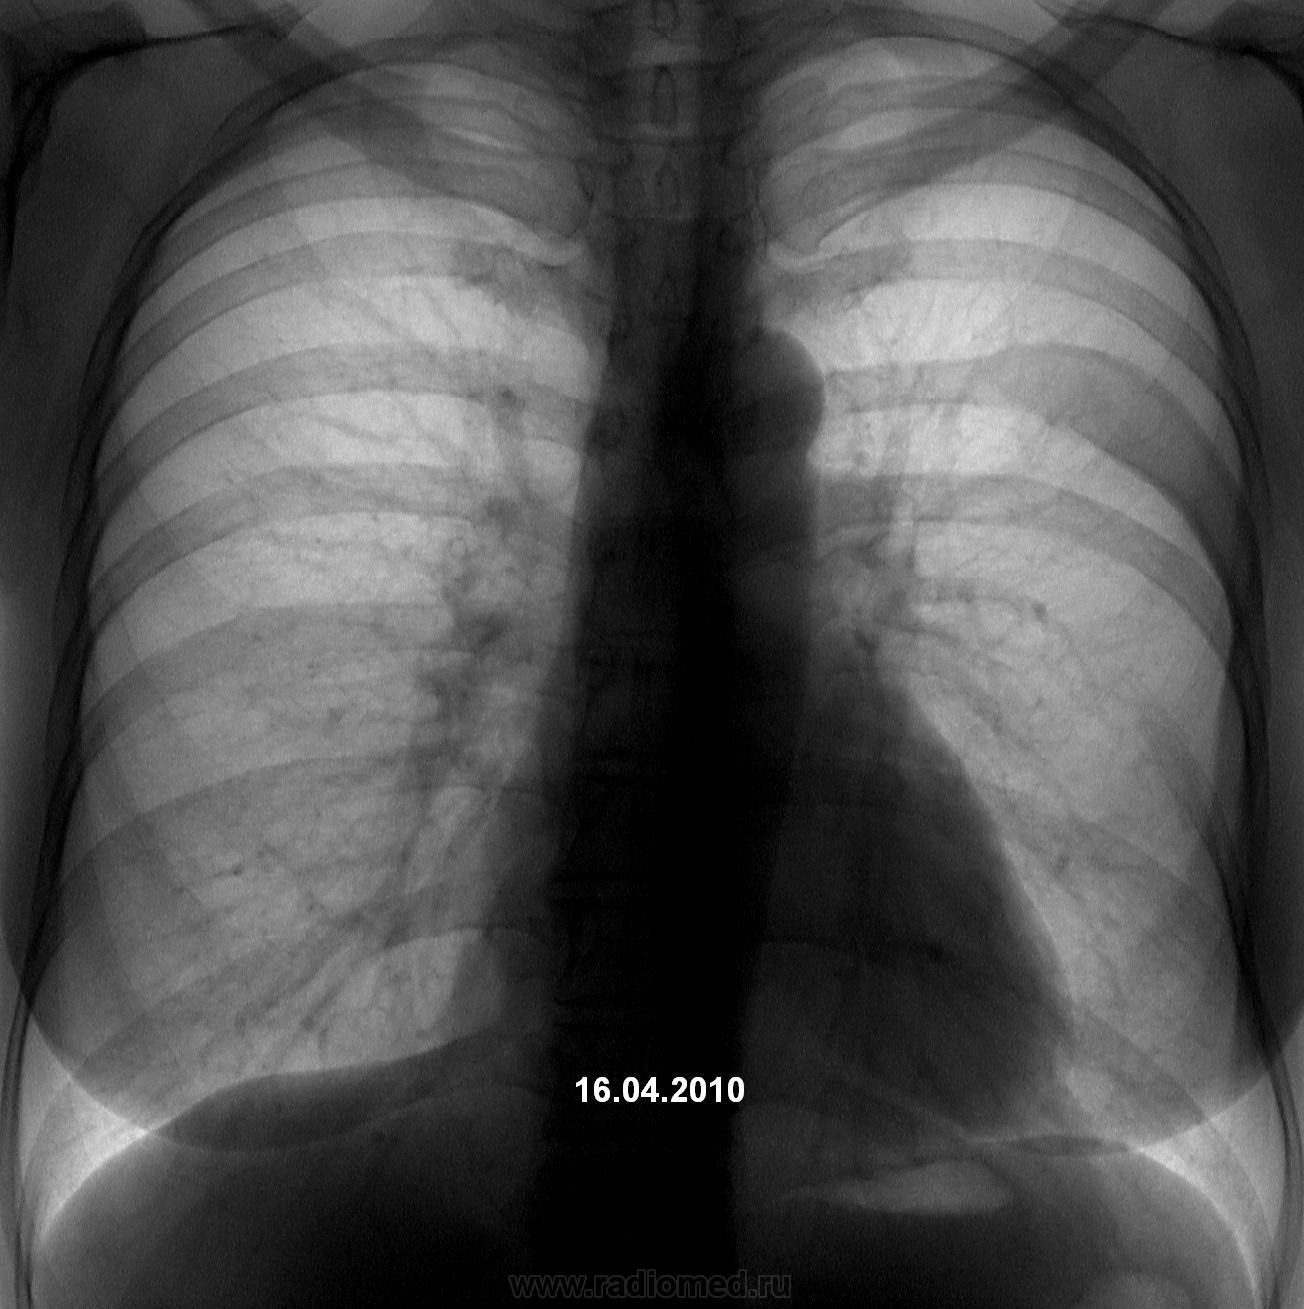

Медицина и диагностика: Аномалии ребер на рентгене